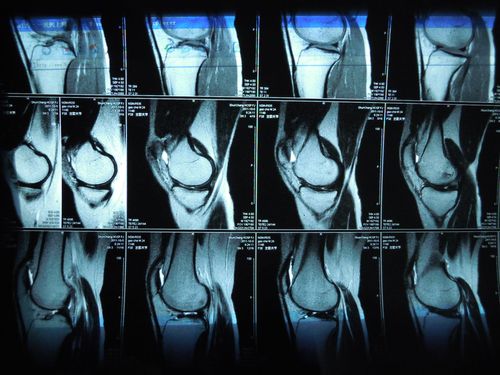

半月板损伤核磁共振图

半月板损伤核磁共振图,半月板损伤静养姿势

膝关节的鉴别诊断 半月板损伤 mri规范化扫描 mri磁共振片子 南昌大学

半月板正常核磁图

半月板损伤磁共振图解

半月板核磁共振图解析

半月板磁共振图解

正常半月板磁共振图解

正常半月板核磁图片

半月板3度撕裂共振图

膝关节半月板损伤图